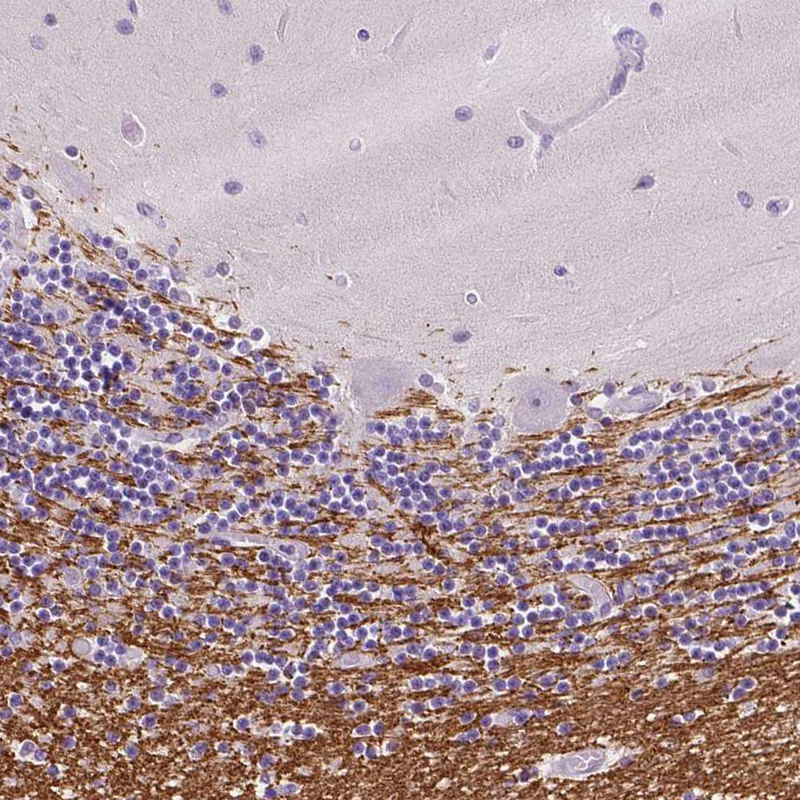

Immunohistochemical staining of human cerebral cortex shows moderate cytoplasmic positivity in oligodendrocytes.